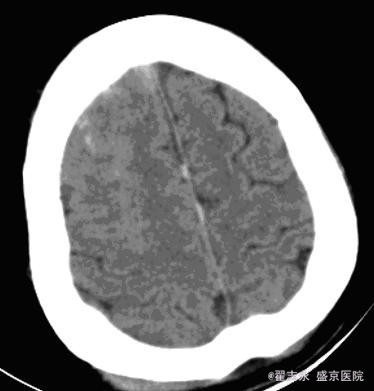

肝炎后肝硬化失代偿期并发脑出血

患者女,55岁。丙肝后肝硬化,全血细胞减少,白细胞计数,2.7*10^9/L,血红蛋白,54g/L,血小板计数,5*10^9/L。突然出现头痛。

2小时后突然意识不清,考虑再出血。后死亡。

脑内出血的可能病因有高血压、动脉瘤、动脉硬化、脑动脉淀粉样变性、动静脉畸形、血液病等。 肝炎后肝硬化失代偿期并发脑出血, 临床症状多不典型, 如果不及时进行仔细检查, 易误诊为肝性脑病或电解质紊乱。肝硬化失代偿期并发脑出血, 发病前无前驱症, 病情进展迅速, 突然发生意识障碍, 出血量大, 病情危重, 病死率高。 发病机制, 可能与下列因素有关: 1、肝炎后肝硬化失代偿期肝功能贮备能力下降, 维生素K 吸收差, 凝血因子和凝血酶原合成障碍, 导致凝血功能下降。2、肝炎后肝硬化失代偿期大多数有脾功能亢进, 继发性血小板减少。3、肝炎后肝硬化失代偿期继发性醛固酮增高, 出现高醛固酮血症, 导致水、钠储留, 器官血流量增加, 内脏血管及全身血管扩张, 处于高动力循环状态, 血管承受的压力大, 易导致脑血管破裂。4、毛细血管脆性增加。 血液病所致脑出血,多位于脑皮层,可能为多处。且血肿不均匀。在血液病未纠正情况下,极容易再出血,再出血量大,死亡率高。